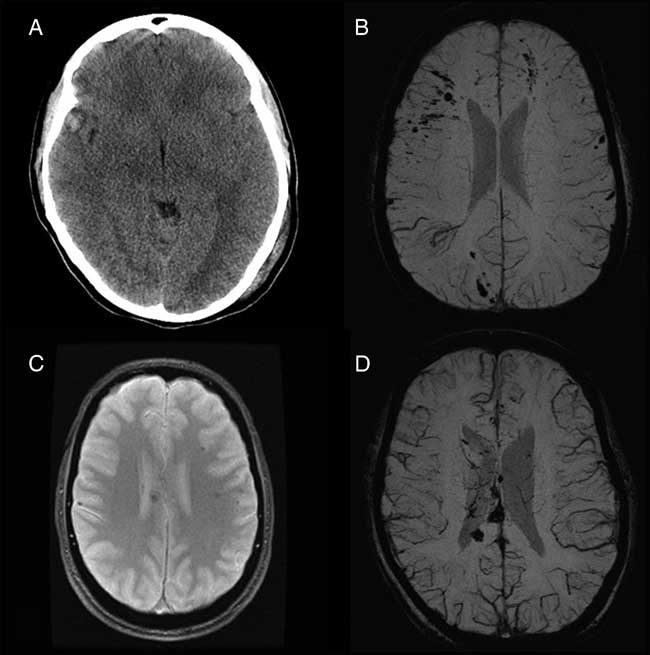

From October 22, 2014, to March 21, 2017, eight adolescent moderate or severe TBI patients were referred to the multidisciplinary pediatric concussion program. Seven patients were offered and agreed to undergo graded aerobic treadmill testing as part of their clinical management. The remaining patient was considered for graded aerobic treadmill testing, but was lost to follow-up before testing could be completed. Overall, the cohort included five females and two males with a mean age of 17.3 years (range, 16-19 years). Mechanisms of injury sustained by these patients included passenger-restrained motor vehicle collision (n=5), passenger-nonrestrained motor vehicle collision (n=1), and a fall from the third story of a building (n=1). Based on earliest reported GCS, one patient was classified as a moderate TBI patient and five were classified as severe TBI patients. Earliest reported GCS was not documented for one patient who was classified as a moderate TBI patient based on clinical history (40-minute loss of consciousness) and neuroimaging findings. Neuroimaging studies demonstrated evidence of structural brain injury in all patients (Figure 1). The most frequent neuroimaging findings were diffuse axonal injury (n=5), traumatic subarachnoid hemorrhage (n=3), intracerebral contusion (n=3), and acute subdural hematoma (n=3). Associated cranial injuries included petrous temporal bone fracture with conductive hearing impairment (n=1), occipital calvarial skull fracture and petrous temporal bone fracture with sensorineural hearing impairment and posttraumatic benign paroxysmal positional vertigo (n=1), stable occipital condyle fracture (n=1), complex maxillofacial and mandibular fractures requiring surgical reconstruction and tracheostomy (n=1), and frontal calvarial skull fracture and indirect traumatic optic neuropathy (n=1). Extracranial injuries among these patients included stable C1 vertebral fracture (n=1), subaxial cervical spine ligamentous injury, T4 vertebral transverse process fracture, spleen laceration (n=1), and nonoperative mesenteric root injury and pulmonary contusion (n=1). Based on physical examination findings, two patients were found to demonstrate subtle right-sided hemiparesis and incoordination, whereas five demonstrated mild impairments on balance testing. For additional features of the study cohort, see Table 1. The one patient diagnosed with posttraumatic benign paroxysmal positional vertigo underwent comprehensive evaluation by a vestibular physiotherapist and successful treatment with canalith repositioning before initial graded aerobic treadmill testing.

Figure 1 Representative neuroimaging findings among pediatric moderate and severe TBI patients who underwent graded aerobic treadmill testing. (A) Axial computed tomography scan in a 17-year-old female moderate TBI patient demonstrates a right temporal contusion (patient 3). (B) Axial susceptibility-weighted magnetic resonance imaging (MRI) scan in a 17-year-old female severe TBI patient demonstrates multifocal cortical and subcortical microhemorrhages consistent with diffuse axonal injury (patient 2). (C) Axial gradient recalled echo MRI in a 19-year-old male severe TBI patient demonstrates multiple hemorrhages within the corpus callosum and white matter consistent with diffuse axonal injury (patient 5). (D) Axial susceptibility-weighted MRI in an 18-year-old female severe TBI patient demonstrates multifocal microhemorrhages within the corpus callosum and white matter consistent with diffuse axonal injury (patient 6).